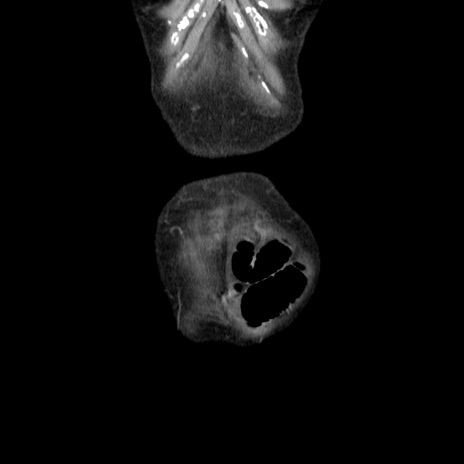

横断像